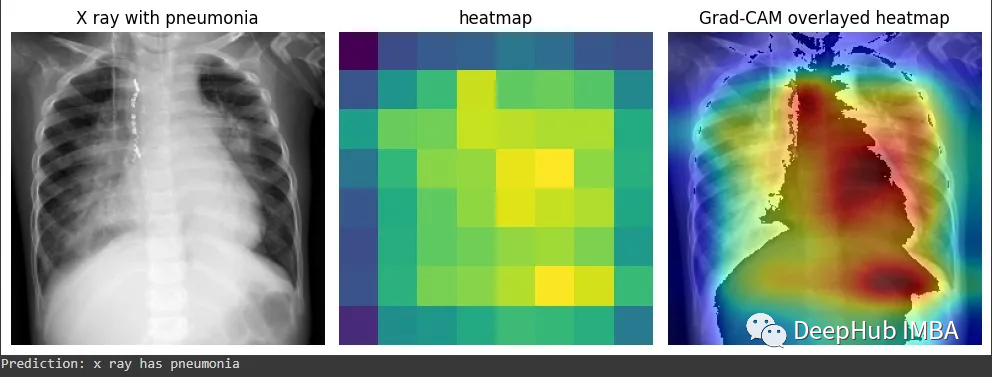

为了演示Grad-CAM的实现,我将使用来自Kaggle的胸部x射线数据集和我制作的一个预训练分类器,该分类器能够将x射线分类为是否患有肺炎。

得到的激活包含1024个特征映射,这些特征映射捕获输入图像的不同方面,每个方面的空间分辨率为8x8。通过钩子获得的梯度表示每个特征映射对最终预测的重要性。通过计算梯度和激活的元素积可以获得突出显示图像最相关部分的特征映射的加权和。通过计算加权特征图的全局平均值,可以得到一个单一的热图,该热图表明图像中对模型预测最重要的区域。这就是Grad-CAM,它提供了模型决策过程的可视化解释,可以帮助我们解释和调试模型的行为。

但是这个图能代表什么呢?我们将他与图片进行整合就能更加清晰的可视化了。

结合原始图像和热图

这样看是不是就理解多了。由于它是一个正常的x射线结果,所以并没有什么需要特殊说明的。

再看这个例子,这个结果中被标注的是肺炎。Grad-CAM能准确显示出医生为确定是否患有肺炎而必须检查的胸部x光片区域。也就是说我们的模型的确学到了一些东西(红色区域再肺部附近)